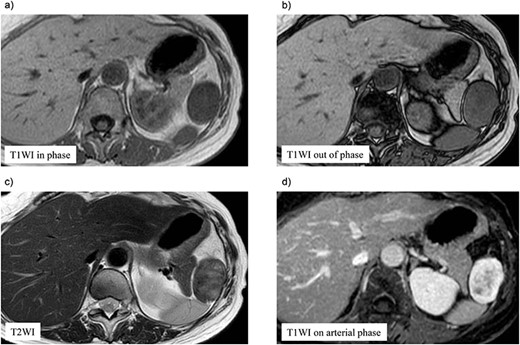

A 70-year-old woman underwent right thyroidectomy for thyroid cancer 7 years ago. An abdominal tumor was incidentally detected on computed tomography (CT) during a follow-up visit, and the patient was referred to our hospital for further evaluation. On physical examination, the mass was nonpalpable and nontender. Laboratory test results were nonspecific. Abdominal contrast-enhanced CT revealed a well-circumscribed soft tissue mass measuring 5.1 × 3.2 × 2.6 cm at the left anterolateral abdominal wall (Fig. 1). There were no signs of invasion of the adjacent organs. Magnetic resonance imaging (MRI) revealed a hypointense tumor on T1-weighted MR images with delayed enhancement in the arterial phase and a heterogeneous hyperintense tumor on T2-weighted MR images (Fig. 2a–d). The tumor was preoperatively diagnosed as a gastrointestinal tumor or a benign tumor, and it was mainly supplied by abdominal wall arteries.

Preoperative magnetic resonance (MR) imaging findings. The tumor shows low signal intense mass on T1-weighted MR images in phase (a) and out of phase (b) and a heterogeneous hyperintense mass on T2-weighted MR images (c). (d) The tumor shows hypointense tumor on T1-weighted MR images with delayed enhancement in the arterial phase.